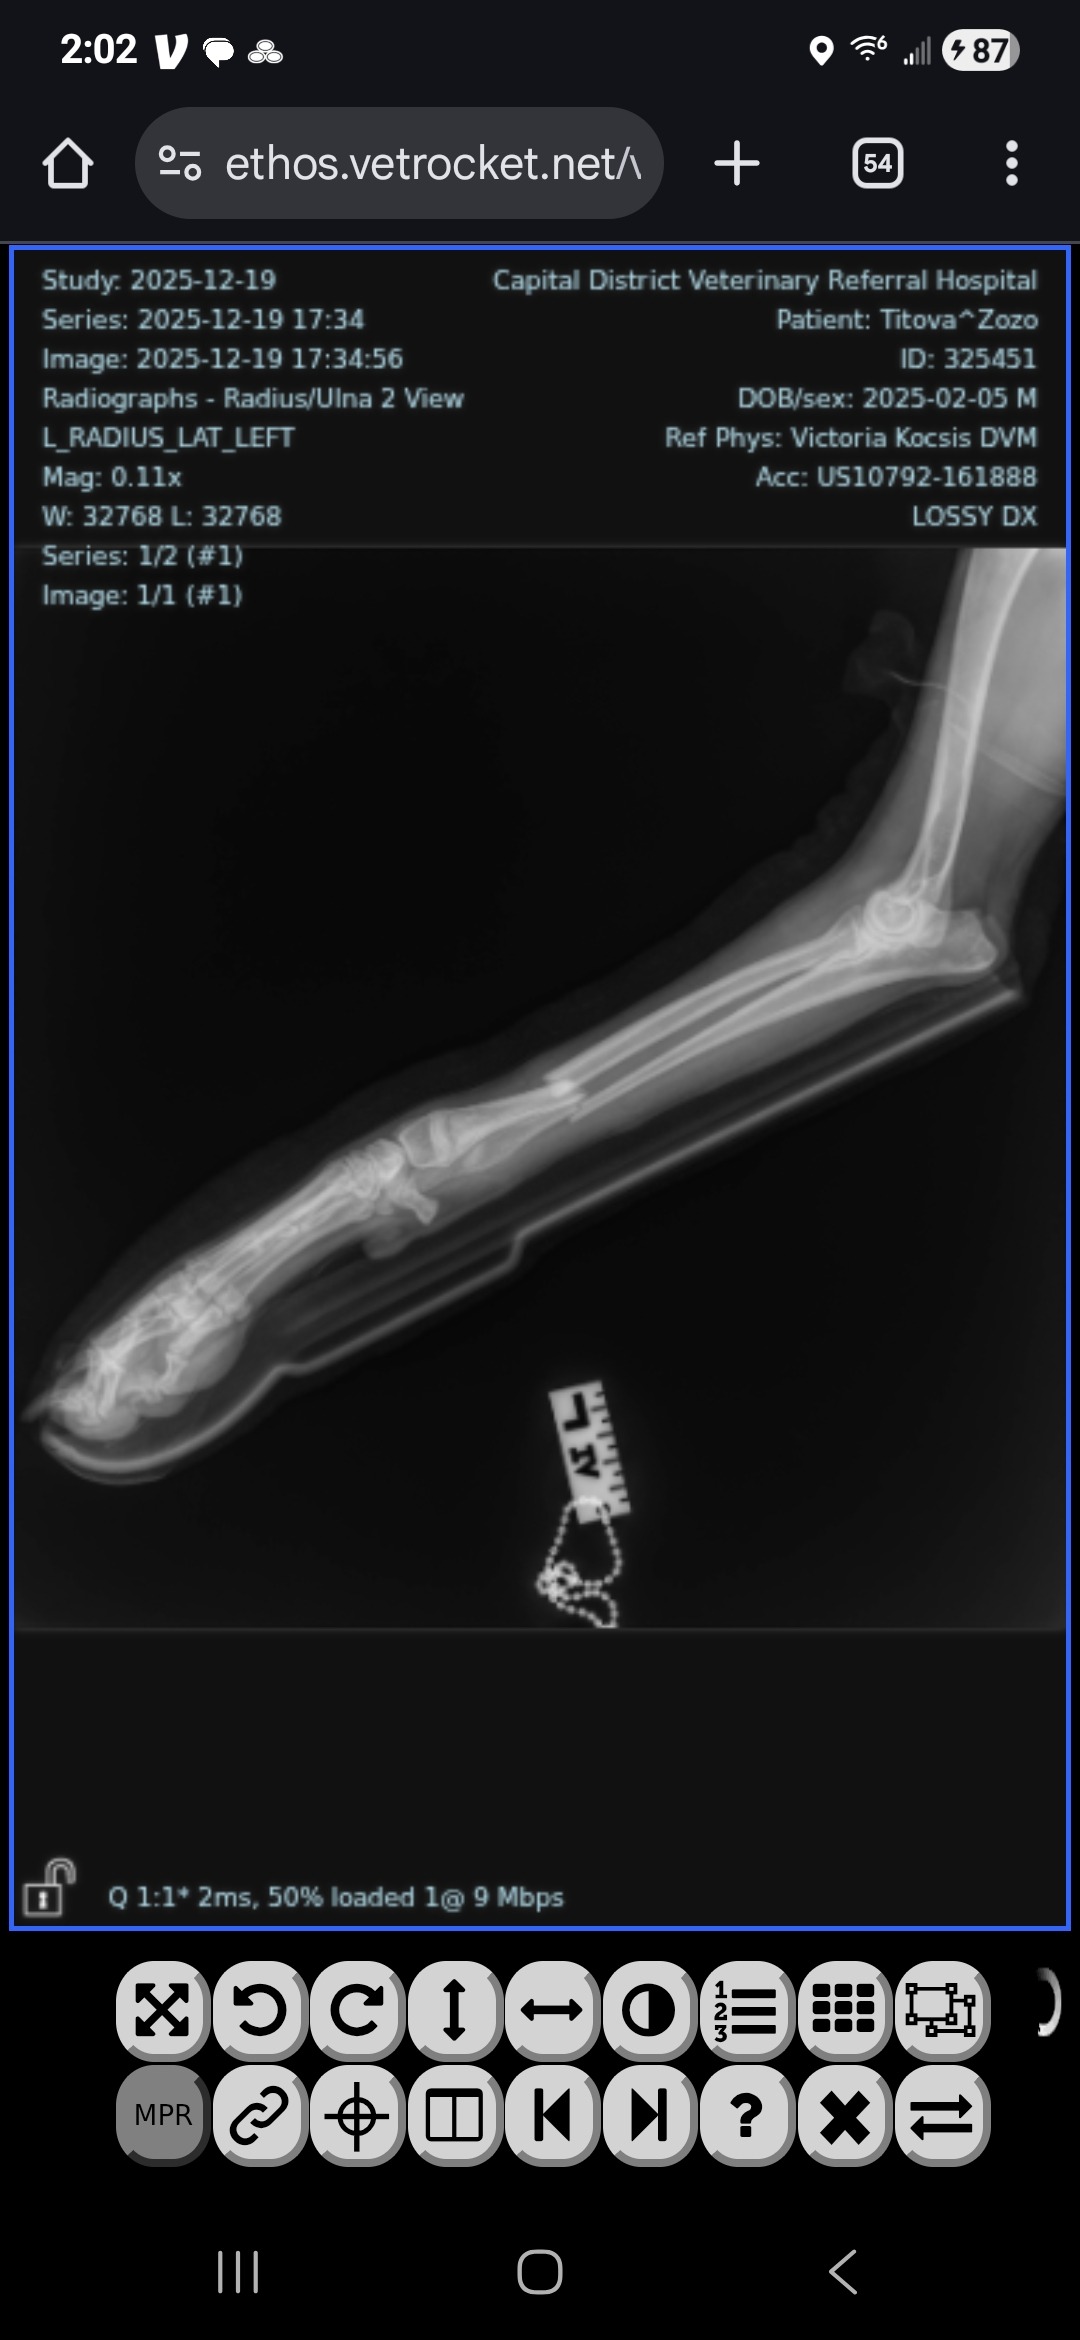

On Thursday overnight, my world turned upside down. Zozo, my 10-month-old Belgian Sheepdog and service dog in training, landed poorly while jumping and broke both bones in his front left leg. He’s just a baby — full of life, curiosity, and joy — and suddenly he’s facing an injury that could permanently change his future.

Right now, Zozo is undergoing weekly sedated re-splints to stabilize his leg. His veterinary team believes he is a strong candidate for surgery, with an excellent chance at healing and living a full, active life — but the surgery must be done within the next 2 weeks to save his leg. The cost of surgery and care is more than I can manage on my own.